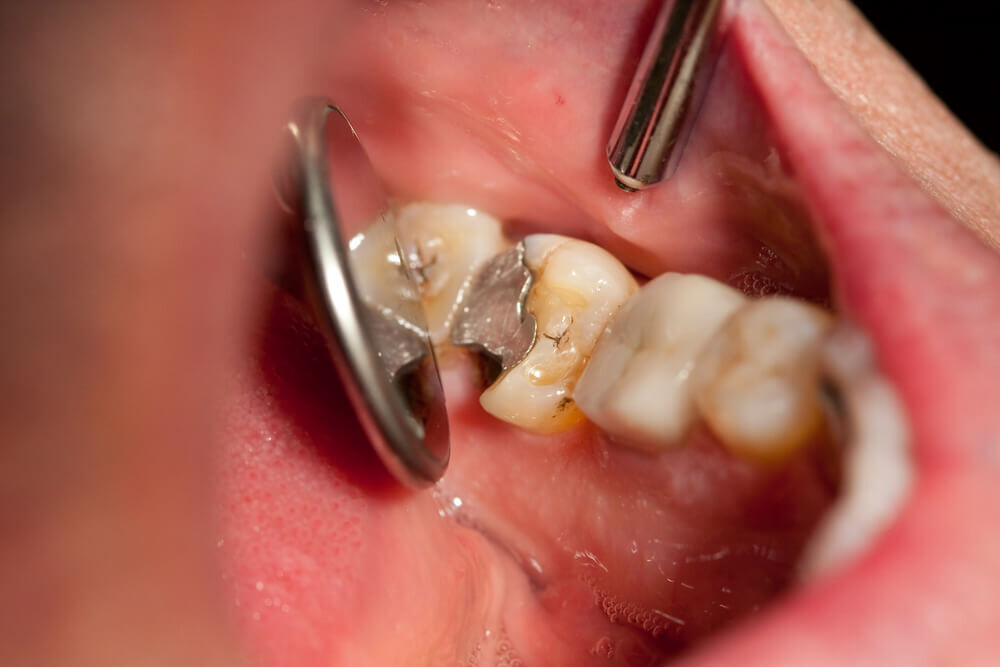

A damaged filling

A damaged filling can cause toothache when the filling is no longer able to protect your tooth from external stimuli. When a filling is damaged, it can create an opening in the tooth, allowing bacteria to penetrate and cause an infection, leading to inflammation, swelling, and pain. Additionally, if you don’t replace the filling in time, it may cause your tooth to weaken or crack. A damaged filling may also cause sensitivity to hot and cold food and drinks.

What does a cavity feel like? In the earliest stages, the answer might be nothing. There are no nerves in your tooth enamel, so when the decay is in that layer, you likely won't feel a thing. Once the decay has progressed enough to reach the softer tissues inside the tooth, where the dentin and nerves are, you might notice signs of a cavity. Your teeth might feel sensitive and you could feel some pain, especially after eating sweets, hot foods or cold foods. The pain can be fairly mild or sharp and intense. Some people with cavities also feel pain when biting down.

Depending on the size of the cavity, you may be able to see evidence of it in your mouth. Cavities sometimes create visible holes in the teeth. They can also create stains that are black, brown or white on the surface of the tooth.

What should you do if you think you have a cavity? The first step is to see your dentist. Although cavities can be reversed in the early stages, by the time you are feeling discomfort or pain, only a dentist can treat them. An x-ray will be taken to determine how the cavity has progressed into the tooth. Depending on how severe the cavity is, you might need a filling to fix it. If the decay is very severe, the dentist might replace the tooth with a crown or perform a root canal.